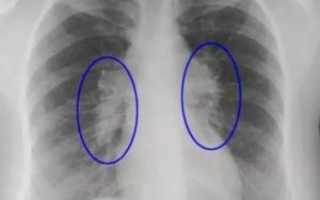

Для диагностики фиброза также используют рентгенологические методы:

- рентгенограмма необходима для визуализации легочного рисунка,

- компьютерная томография дает возможность увидеть очаговые, периферийные, субплевральные, сетевидные затемнения органа,

- эхокардиограмма нужна для подтверждения легочной гипертензии.